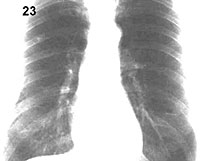

Placa 24

En este caso la TAC muestra el nódulo en forma mucho más evidente y como su densidad es similar a la de la vértebra y mayor que la de la aorta, se puede concluir que se encuentra enteramente calcificado, hecho que no es evidente en la placa radiográfica y que certifica su benignidad.